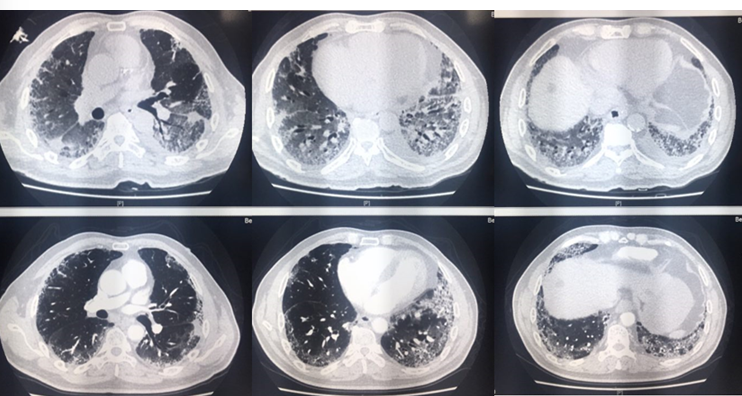

图3为AEP患者的胸部CT,可见相对较为松散的实变,另有小叶间隔增厚以及部分纤维病灶形成。患者经历了较长的诊断过程,抗感染效果不好,最终通过活检病理明确诊断。

图3  AEP患者胸部CT

图4为AFOP患者的胸部CT,表现为双肺大片实变。该患者症状较重,病情进展迅速,抗感染效果不佳,最终依靠病理诊断明确。

图4  AFOP患者胸部CT